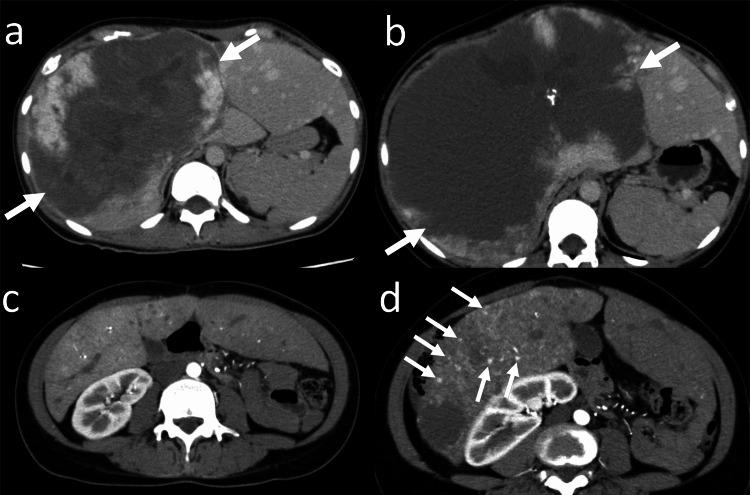

Computed tomography (CT) and magnetic resonance imaging (MRI) reports at Kyoto University Hospital, Kyoto, Japan, between January 2001 and March 2023 were retrospectively searched to find adult patients with hepatic hemangiomas >10 cm. Patients who were followed up without treatment for over six months were included. The maximum diameter of the hepatic hemangioma was compared between the baseline and the final CT or MRI. The clinical course of the patients was evaluated.

Twenty-two patients (17 women, five men; median age, 51 years) were identified. The median diameter of hepatic hemangiomas in the baseline study was 114 mm. Two patients had abdominal distention at the time of the baseline imaging, whereas the others were asymptomatic. After follow-up without treatment (the median; 95.5 months), enlargement, no change, shrinkage of hepatic hemangioma was observed in six, 11, and five patients, respectively. The median growth rate of hepatic hemangiomas was 2.5 mm/year. Two patients underwent liver resection for hepatic hemangioma, while the others were followed up without treatment. In four patients, symptoms appeared or worsened. Two patients died: one patient died from prostate cancer progression; the cause of death for the other was not confirmed.